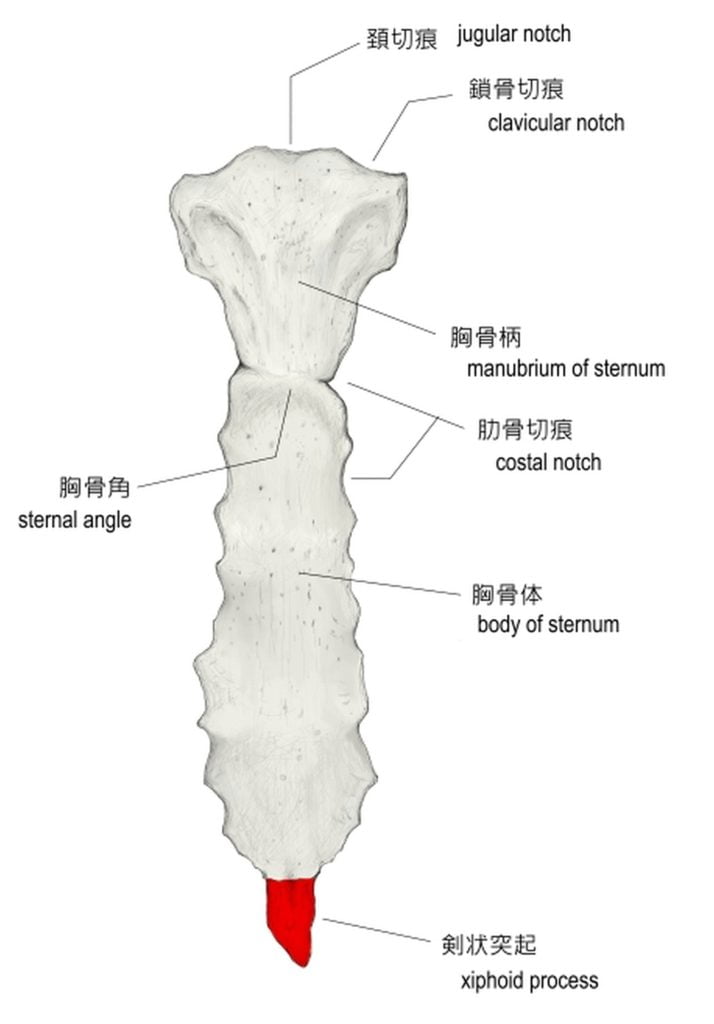

分析出来る事は,相手の肋骨の直下,つまり,みぞおちの上の骨,

"剣状突起部位"と自分の"ひざの皿"が当たったのではと推測しています。

もしくは,

この予想は考えたくないですが,

相手の”浮遊肋骨"部=肋骨の最下部

と自分の膝が当たった可能性も否定は出来ない。

そうなると相手側が"骨折"した可能性が高い。

"浮遊肋骨"という左右2対の肋骨の場所は

胸骨に接しずに浮いているため,

強い外力が及ぶと"折れやすい"のです。